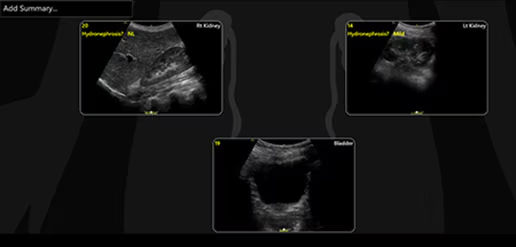

Quickly assess kidneys and the bladder with Renal Diagram

Simplify documentation and provide easy follow up for patients with suspected hydronephrosis. No need to type findings; simply assign a label from a pre-populated list that correlates with images.

renal-diagram-review-desktop